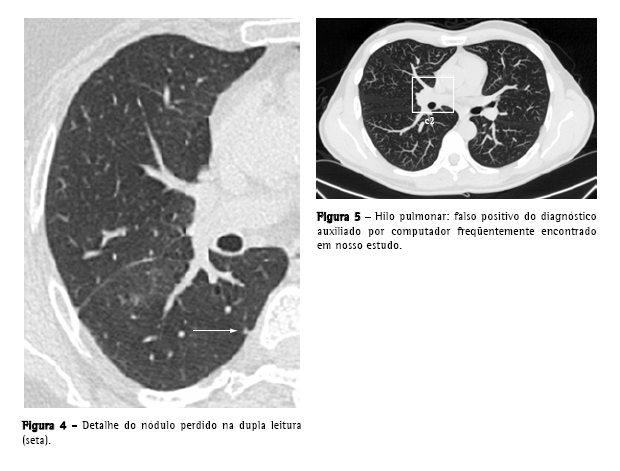

Apenas um nódulo verdadeiro (<1% do total de nódulos verdadeiros), que foi destacado pelo DAC, não havia sido registrado no processo de dupla leitura das imagens. Este era subpleural, mal definido, media 4 mm, e localizava-se no lobo inferior direito (Figura 4).

A média de falsos positivos por exame (10,9), apesar de estar dentro da faixa encontrada em outros estudos, que varia entre 3 e 13 falsos positivos por TC de tórax,(21) não é desprezível, sendo um fator de desgaste e que consome tempo na revisão dos dados fornecidos pelo computador. Os falsos positivos encontrados foram, principalmente, estruturas vasculares, e estão de acordo com os referidos na literatura, exceto pelas estruturas hilares (Figura 5), que não são especificamente citadas com freqüência.(9,19,22)